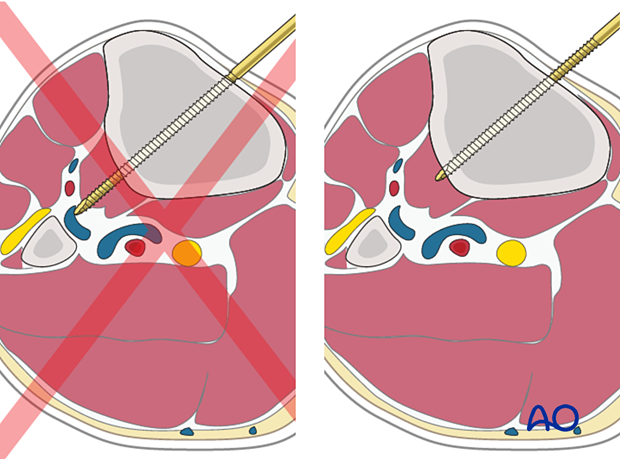

Schanz pins in the tibia are generally placed from the medial side (anteromedially, direct medial, or posteromedial). Pin divergence within the safe zone helps to optimize biomechanical stability of the frame.